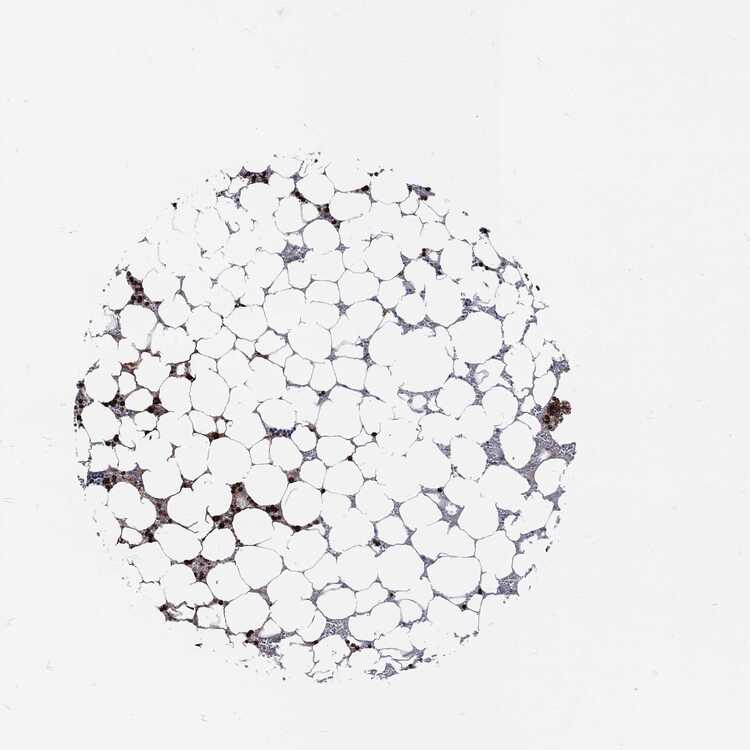

BONE MARROW - Antibody stainingi

Antibody staining in the annotated cell types in the current human tissue is reported as not detected, low, medium, or high, based on conventional immunohistochemistry profiling in selected tissues. This score is based on the combination of the staining intensity and fraction of stained cells.

Each image is clickable and will lead to virtual microscopy that enables deeper exploration of all samples and also displays staining intensity scores, fraction scores and subcellular localization as well as patient and tissue information for each sample.

Antibody HPA021147Antibody HPA061464Antibody CAB000059Antibody CAB080352Antibody CAB080353Antibody CAB080354

Hematopoietic cells LowHighMediumHighHighHigh